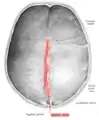

Human adult skull from above.

Human adult skull from above. Sagittal suture labeled at center.

The sagittal suture, also known as the interparietal suture and the sutura interparietalis, is a dense, fibrous connective tissue joint between the two parietal bones of the skull. The term is derived from the Latin word sagitta, meaning arrow.

The sagittal suture is formed from the fibrous connective tissue joint between the two parietal bones of the skull.[1] It has a varied and irregular shape which arises during development.[1] The pattern is different between the inside and the outside.[1]